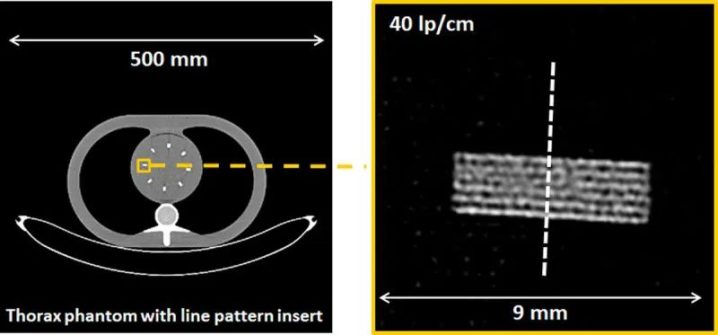

图4显示了市售PCD-CT与第三代DSCT的探测器结构对比。探测器像素大小为0.275×0.322mm2(等中心为0.151×0.176mm2)。每组4×6探测器像素通过一个二维准直器网格与相邻组隔开,以减少散射辐射。使用这种探测器和0.4×0.4mm2的焦点,可以实现超过40 lp/cm的分辨率,相当于0.125mm,见图5;这大约是EID-CT系统分辨率的两倍。在CT中,空间分辨率的提高总是伴随着图像噪声的增加或辐射剂量的相应增加;CT的这一基本规律也适用于PCD-CT。因此,必须采用基于迭代或深度学习的精细降噪技术。

图5 在PCD-CT上实现40lp/cm空间分辨率的演示,探测器示意图如图4所示。在重建过程中,使用了最锐利卷积核Br98。